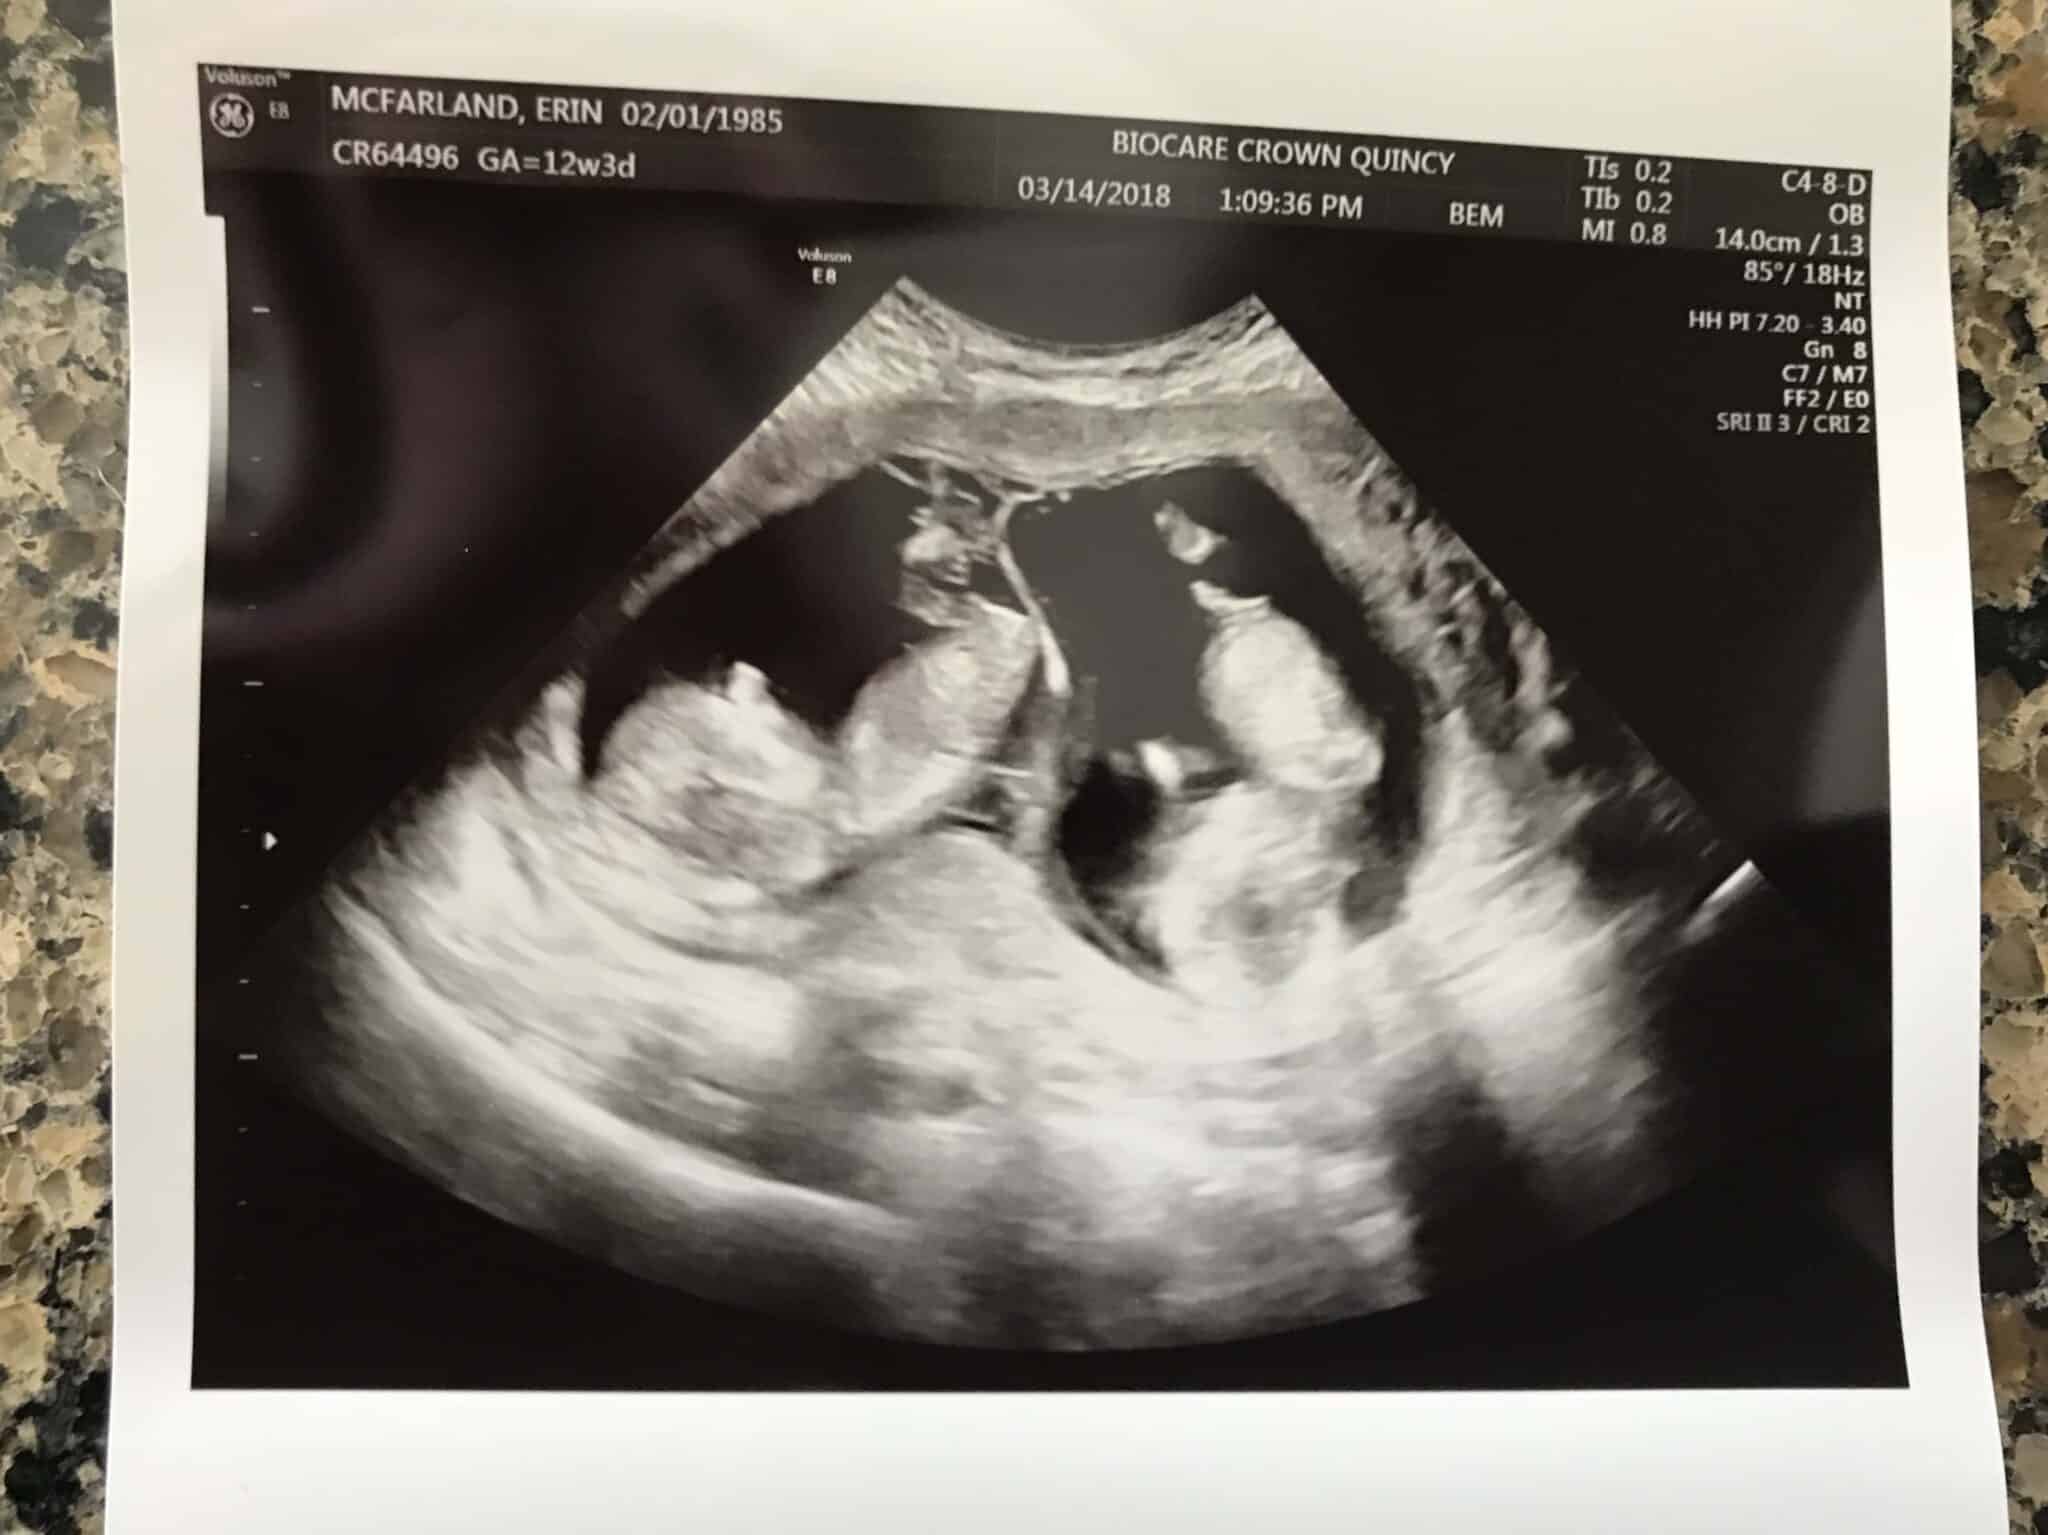

Ultrasound Photos at 12 Weeks Pregnant With Twins